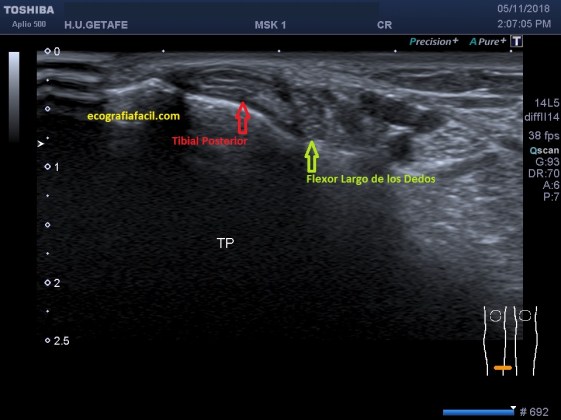

En el corte axial, a la altura del tercio distal de la tibia se ve como va unido a otro tendón, es muy importante discriminarlos y estudiarlos independientemente.

Tendón Tibial Posterior: Este tendón se estudia desde el tercio medio y distal de la tibia por su cara interna y posterior justo detrás de la Tibia, es el que va pegado a ella, pero muy cerca de él está el Flexor de los Dedos que nos puede llevar a equívoco en la exploración, la clave es saber situarlos, el que nos interesa es el que va pegado a la Tibia.

Siempre vital saber que estamos en el tendón deseado y no en otro que discurra a su lado.